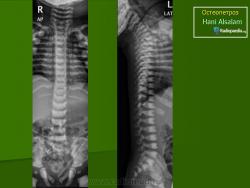

Морфологические изменения при остеопетрозе объясняются недостаточной активностью остеокластов. Макроскопически видно, что кости теряют костномозговой канал, концы длинных костей приобретают грушевидную форму (колбовидная деформация). Невральные отверстия становятся маленькими и сдавливают выходящие нервы. Первичная спонгиоза, которая удаляется в ходе начального роста, остается и заполняет полость костномозгового канала. Она не оставляет места для кроветворной части костного мозга и препятствует формированию зрелых костных балок. Формирующаяся кость не восстанавливает естественные структуры и имеет тенденцию к сохранению в грубоволокнистом состоянии. В конечном итоге эти внутренние аномалии делают кость хрупкой. Гистологически существенных изменений в количестве остеокластов обнаружить не удается, их число может быть чуть увеличенным, нормальным или уменьшенным.

Мраморная болезнь (болезнь Альберс-Шенберга) - семейный генерализованный остеосклероз, протекающий с лейкемической реакцией крови у детей, с анемией и лейкопенией у взрослых, нередко с атрофией зрительных нервов и глухотой. Характерны деформация мозгового и лицевого черепа, заращение придаточных полостей носа плотной бесструктурной костной тканью. Ввиду постепенного сужения отверстий в черепе и межпозвонковых отверстий могут возникать полиморфные проявления поражения периферической нервной системы как на черепном, так и на позвоночном уровнях. В позвонках костные балки губчатого вещества утолщены и уплотнены. В трубчатых костях отмечается сужение, а затем и исчезновение костномозговых полостей, эпифизы булавовидно утолщены и поперечно исчерчены, имеется склонность к патологическим переломам. Наследуется по аутосомно-рецессивному типу и тогда, проявляясь в фенотипе в первые годы жизни, быстро приводит к смерти, или же - по аутосомно-доминантному типу, проявляясь в 20-40-летнем возрасте. Описал болезнь в 1907 г. Н.Е. Albers-Schonberg.